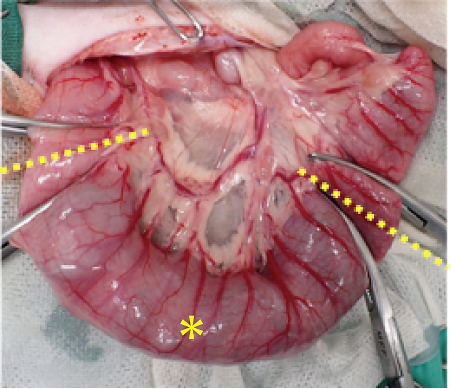

(手術画像:太くなった結腸を引っ張り出しています。黄色点線の部分で切断し、中央の✳︎部分の結腸を取り除きます。)